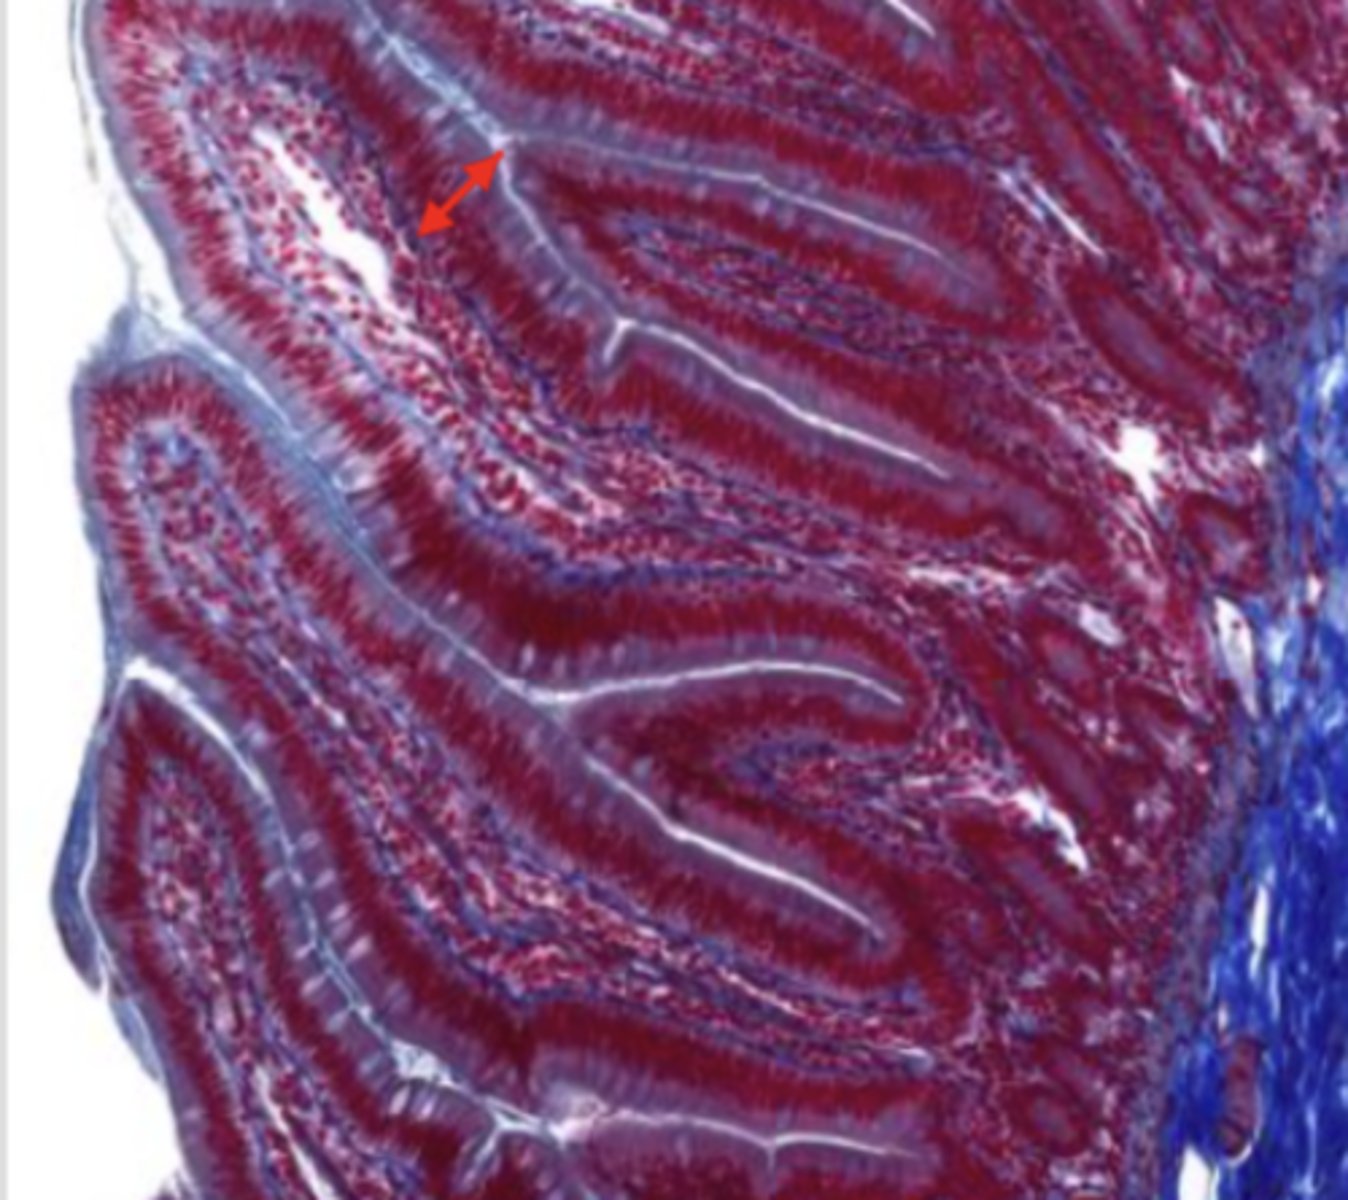

colon (histology)

simple columnar epithelium

what kind of epithelium lines the mucosa of the colon?

intestinal glands/crypts (colon)

lumen (colon)

mucosa (colon)

mucosal epithelium (colon)

lamina propria (colon)

muscularis mucosa (colon)

submucosa (colon)

contains glands and blood supply

muscularis externa (colon)

serosa/adventitia (colon)